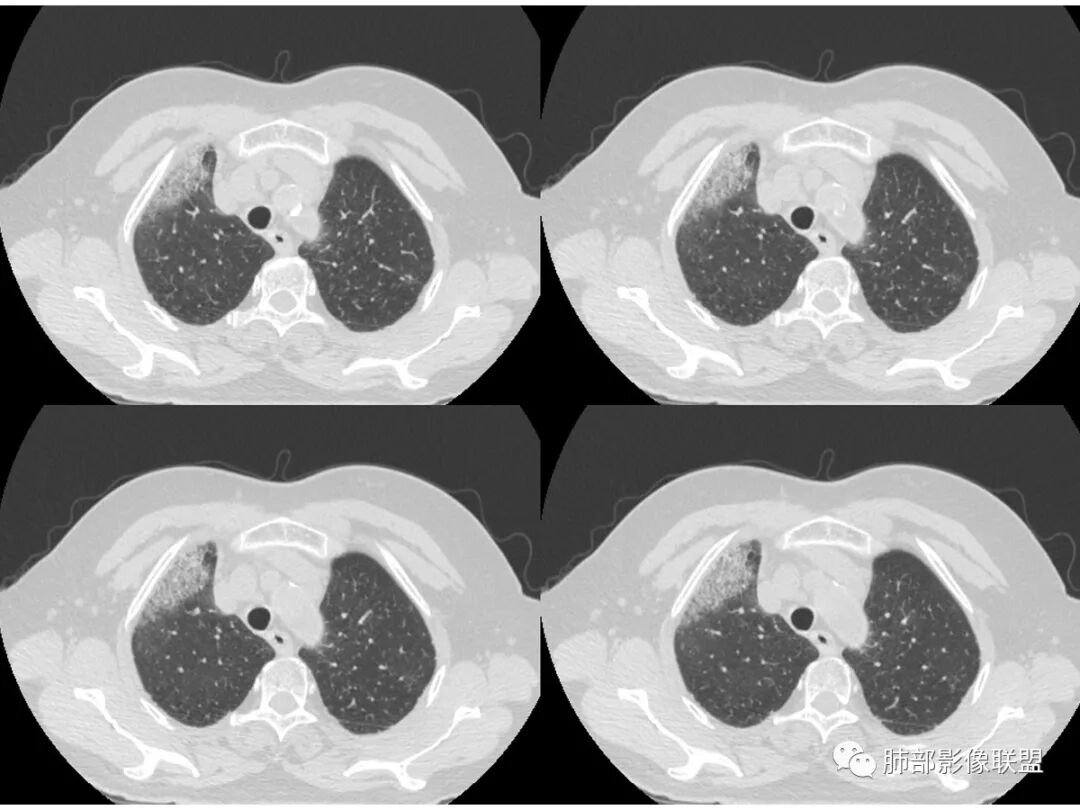

右肺上叶大片状阴影,内见僵硬的支气管,部分支气管轻度扩张,内见一空洞和液平,病灶边缘可见磨玻璃影,首先考虑恶性病变,粘液性腺癌伴感染可能。

老年女性,慢性病史,白色痰液,量多,病灶起于胸膜下,实性加磨玻璃,磨玻璃边缘偏轻,跨叶生长,病灶内可见枯树枝,考虑肺炎型肺癌。

老年女性,右肺上叶大片实变及磨玻璃密度影,磨玻璃边缘清晰,内可见小叶间隔增厚,内可见空洞,似可见分隔,叶间裂局部膨隆,纵膈窗,没有增强,枯树枝不明显,肺炎型肺癌可能,鉴别大叶性肺炎,结核?

胸CT:右肺上叶实变内可见支气管充气征,近端支气管狭窄,远端扩张,周围可见毛玻璃影,右肺中叶支气管闭塞,并可见气道壁钙化,右肺中叶体积缩小,实变内可见空洞,并可见气液平面,空洞周围可见毛玻璃样影,右肺下叶支气管开口狭窄,右肺门淋巴结肿大。纵隔窗可见病灶与壁层胸膜间隙增宽,考虑良性病变-----感染性病变------TB?

老年女性,右肺中上叶病灶,血象不高,血沉高,TB dna阴性,上叶尖端病灶,紧贴胸膜,边界似清非清,中间可见实变,内见枯树枝征,首先考虑粘液腺癌可能性大。患者右肺中叶见空洞、气液平,病灶没多发空洞,可见气液平,考虑合并TB感染。

老年女性,无诱因咳嗽咳痰,白色粘液痰,抗炎治疗无好转,右肺多叶磨玻璃影,其内见枯树枝征,磨玻璃边界清,中间见实变影,且部分实变影内见空洞或局部支气管扩张,内壁光整,无纵隔淋巴结肿大,常规考虑粘液性腺癌,感染性病变待排,细菌性的排除,白细胞不高,不太支持,建议支气管镜检。

1.右上肺大片状影,周围有磨玻璃影,支气管截断征、枯枝征、远端支气管充气征,可见多个大小不等囊泡(支气管阻塞活瓣作用形成),病灶有少许收缩力感,叶间裂被稍牵拉内移;

病史老年女,白痰;影像实变,ggo多数边界清,病灶下缘部分不清,枯树枝,支气管近端阻塞、僵硬,病灶跨叶;病灶内空洞,有液平;间质增厚有结节感;肺炎型肺癌大于干酪性肺炎。

老年女性,慢性病程,咳嗽伴白色粘液痰,无发热腹痛,糖尿病,白细胞及C反应蛋白不高,血沉快,铁蛋白高。胸部CT,右肺上叶大片状实变伴磨玻璃密度影,边界不清,边缘局部膨隆,叶裂弧形下坠,实变影宽基底与胸膜相贴;右肺下叶前基底段见类似病灶;右肺中叶不张并空洞形成,空洞内见气液平面;综合考虑右肺上叶及下叶肺炎型肺癌,右肺中叶结核。

老年女性,病史1月,右肺上中叶大片状影,跨叶,上叶为主,磨玻璃为主,边界模糊,部分实变,内见空洞影和液气平面,壁光滑,支气管开口狭窄,局部有扩张,右肺门淋巴结钙化,首先考虑感染性病变,结核可能,鉴别粘液腺癌。

老年女性,亚急性起病,右肺上中叶大片状影,跨叶,上叶为主,磨玻璃为主,边界模糊,部分实变,内见空洞影和液气平面,壁光滑,洞内可见结节形成,局部有扩张,首先考虑感染性病变,结核可能;洞内可见结节样病灶,鉴别合并曲霉、肿瘤。

患者老年女性,亚急性起病,胸部CT:右肺上叶大片实变,可内见坏死性空洞,可见mGGO,GGO边缘清晰,局部彭隆,内见支气管充气征,可惜没增强,粘液腺癌要考虑,但病灶明显是内朝外不支持,综合考虑结核,建议查痰找抗酸杆菌、气管镜

老年女性,咳白色粘液痰,右肺跨叶大片高密度影,密度不均匀,其内见支气管枯树征,有空洞,边缘部分清楚,叶间裂有下坠膨隆感。考虑粘液腺癌,鉴别干酪性肺炎